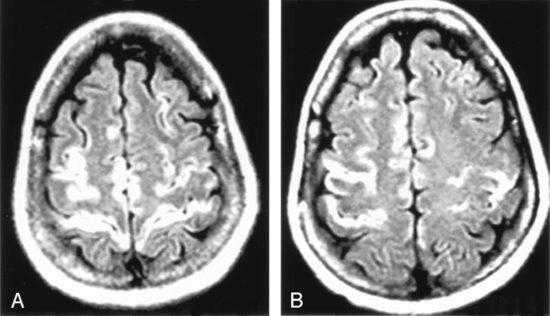

При герпетическом энцефалите на МРТ характерно поражение медиальной области височных долей, нижней поверхности лобных долей и островковой коры. Реже вовлекается корковое вещество затылочных долей, поясная извилина. Иногда поражается конвекситальная поверхность полушарий мозга. На ДВИ определяют ограничение диффузии среди элементов лимбической системы.

Для наиболее раннего выявления энцефалита рекомендуют выполнение мультипланарной МРТ в режиме Т2-ВИ, FLAIR или ДВИ, исследование с контрастом в режиме Т1-ВИ. При этом изменения на МРТ обнаруживают раньше, чем на КТ на 1 - 2 суток. Также на МРТ изображениях больше видны последствия кровоизлияний спустя 7 дней от появления симптомов.

МРТ в 90 % случаев выявляет ранние частые признаки герпетического энцефалита - симметричное поражение медиальных областей теменной доли с преимущественным поражением серого вещества. Это помогает вовремя поставить диагноз, назначить правильное лечение, спасти жизнь больного и уменьшить риск осложнений.